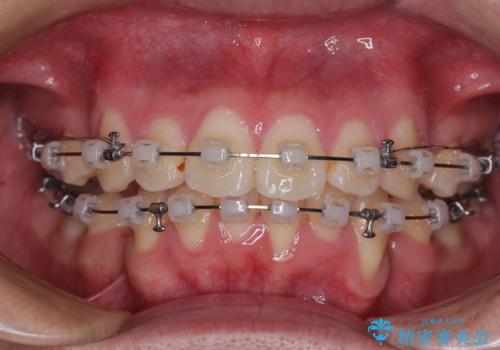

- クリアブラケット

- 1年6ヶ月

- 10-30回